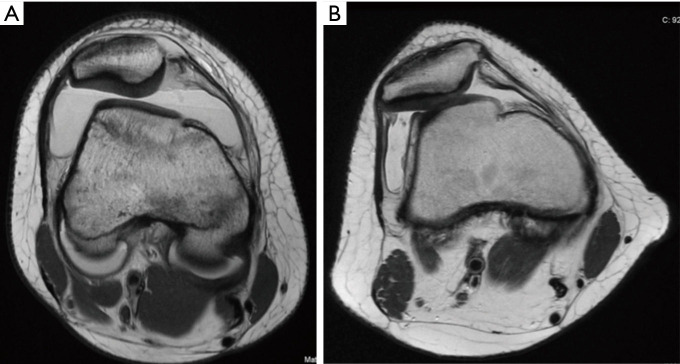

Patellar instability is a common clinical problem that primarily affects the adolescent and young adult population. The demographic and anatomic risk factors that predispose patients to patellar instability are multifactorial and include young age, female sex, trochlear dysplasia, elevated tibial tubercle to trochlear groove distance (TT-TG), patella alta, femoral and tibial malalignment, ligamentous laxity, and lack of neuromuscular control. There have been substantial efforts to predict which patients who sustain a first-time dislocation will go on to incur additional dislocations. This is particularly important because with each dislocation event, there is a significant risk of injury to the patellofemoral joint including both medial patellofemoral ligament (MPFL) stretch or rupture and damage to the cartilage which can range from simple fissures to full-thickness cartilage defects and osteochondral fractures. Prediction models have demonstrated that amongst first time dislocators, young patients with trochlear dysplasia are at the highest risk for redislocation. The current standard of care for treatment of first-time dislocators without a loose body or osteochondral fracture is nonoperative management. However, recently there has been a focus on implementing a risk-stratified approach to the surgical indications for a first-time dislocator as the high-risk population might be better treated with early surgical stabilization to prevent or reduce their risk of recurrent dislocation and its associated morbidity. Likewise, for patients with recurrent dislocations, it remains to be determined whether an isolated MPFL reconstruction is sufficient for high-risk patients with several poor prognostic risk factors or if bony realignment procedures should be implemented concurrently.